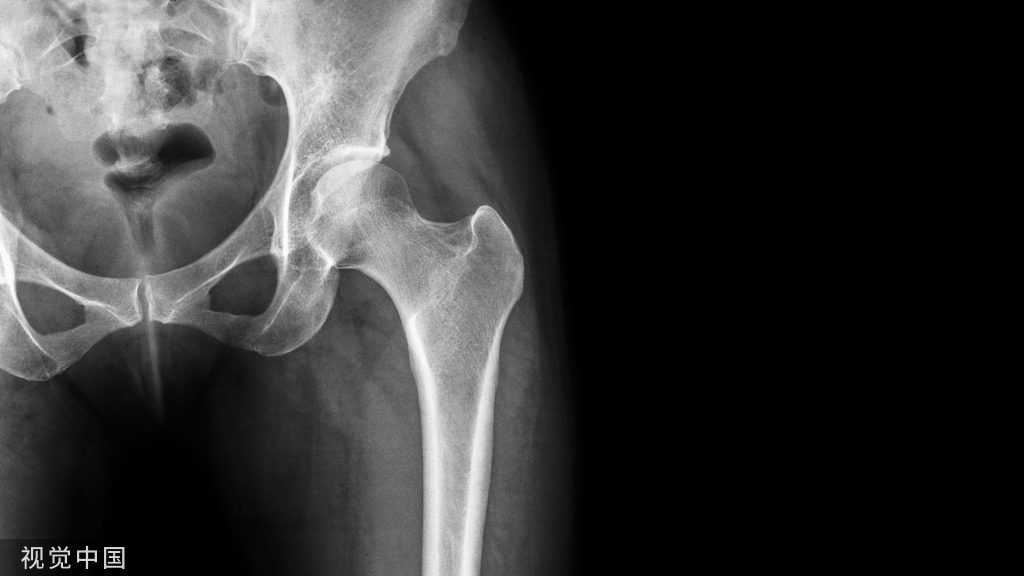

男性吸烟者的骨质疏松风险较高

一项研究称,男性吸烟者的骨质疏松风险高于其他男性,甚至高于女性吸烟者。该数据还显示,如果男性患有骨质疏松且出现髋部骨折,他们的病情将比女性更严重。